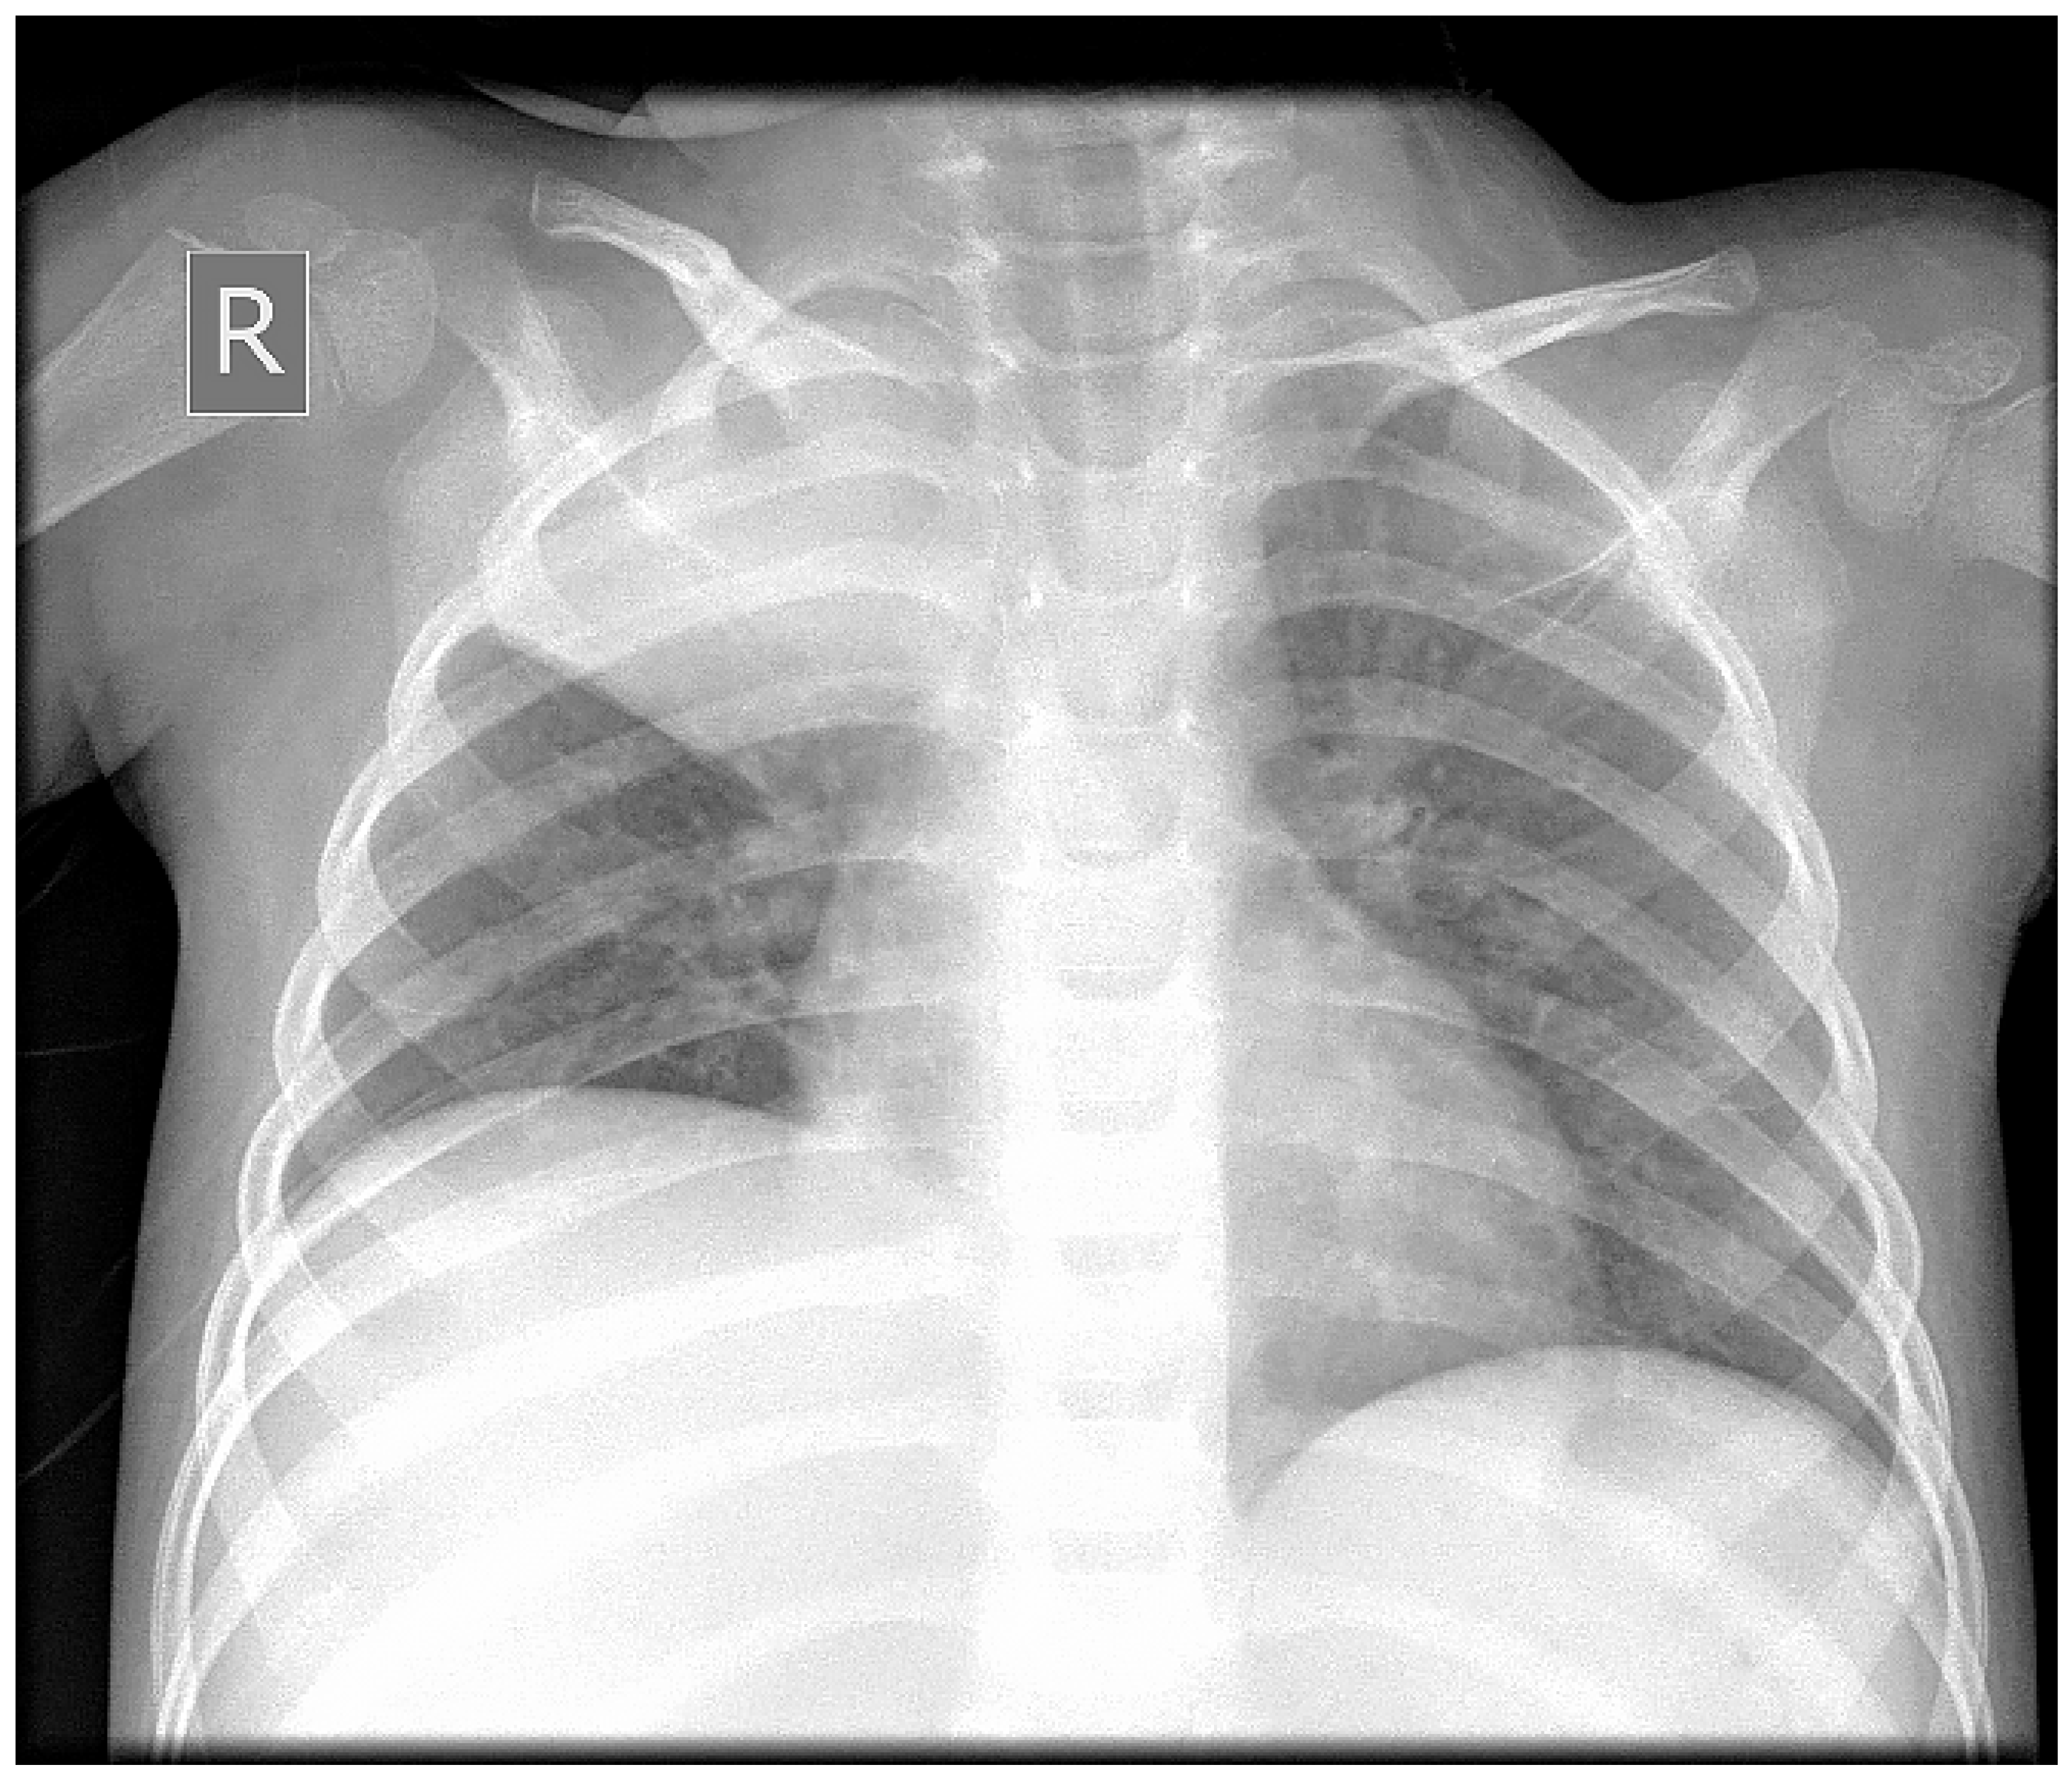

A Rare Case of Rhizomucor pusillus Infection in a 3-Year-Old Child with Acute Lymphoblastic Leukemia, Presenting with Lung and Brain Abscesses—Case Report

2. Case Report

Pahnev, Y.; Avramova, B.; Gabrovska, N.; Dontcheva, Y.; Tacheva, G.; Minkin, K.; Kreipe, H.; Yurukova, N.; Penkov, M.; Kartulev, N.; et al. A Rare Case of Rhizomucor pusillus Infection in a 3-Year-Old Child with Acute Lymphoblastic Leukemia, Presenting with Lung and Brain Abscesses—Case Report. Infect. Dis. Rep. 2026, 18, 2. https://doi.org/10.3390/idr18010002